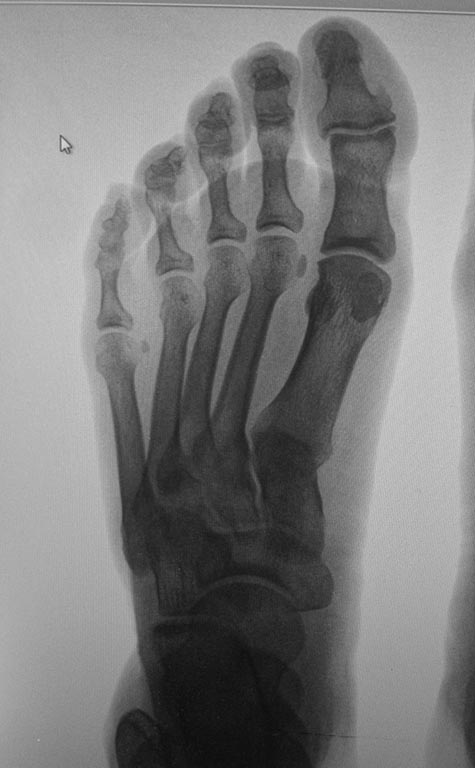

Обратилась женщина с жалобами на выраженную боль, натоптыши в области проксимальных межфаланговых суставов V пальцев стоп.

У больной имеется деформация Тейлора ( угол М4М5 11.5 с двух сторон под нагрузкой). В области пятого плюснефалангового сустава деформация. Боли, гиперемии нет.

Достаточно ли в данном случае остеотомии пятой плюсневой кости с нормализацией угла М4М5 и укорочением?

Если еще актуально, то болезни портных тут не видно. А боль может быть связана с давлением на мозоли, образовавшиеся поверх выпуклостей на тыльнолатеральной поверхности головок основных фаланг пятых пальцев или оснований средних фаланг. Ситуация достаточно частая. Сориентироваться легко под ЭОПом. Или с помощью рентгена с метками, если нет ЭОПа. Можно инъекционную иглу воткнуть до упора в выпуклость и сделать снимок. Чтобы избежать позиционных искажений. А потом убрать эти выпуклости. Чрескожно или открыто, в зависимости от возможностей.